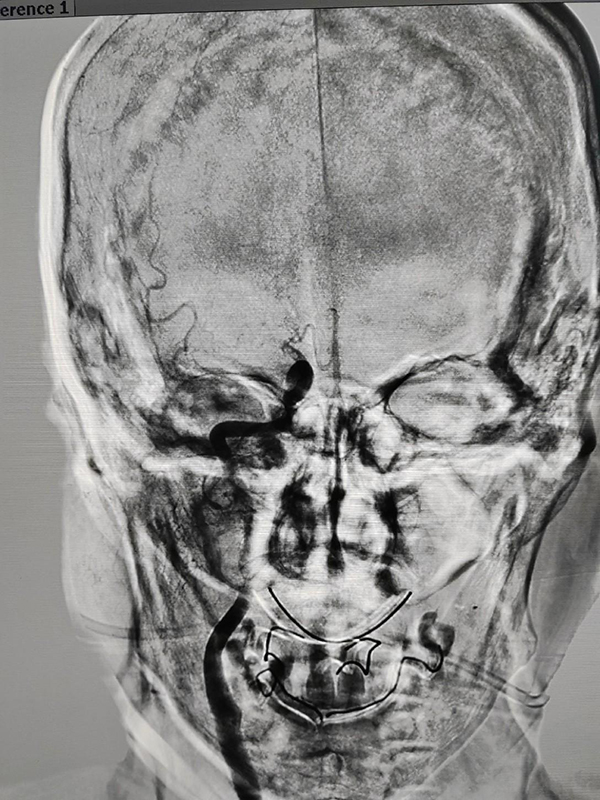

CTP检查结果提示,姬阿姨颅内核心梗死体积约9.6ml(红色区域),但低灌注区域体积高达81ml(绿色区域)(图2),低灌注区域越大,代表可挽救的脑神经细胞越多,手术开通的价值越大,可见患者颅内低灌注区域远远大于核心梗死区域,颅内动脉取栓术手术指征进一步明确。在与患者家属积极沟通,征得家属同意后,王建峰主任团队在国家级高级卒中中心李健主任的指导下,急诊进行了全脑血管造影术+颅内动脉取栓术,术中证实右侧大脑中动脉起始段闭塞(图3),并急诊进行了右侧大脑中动脉取栓术,术中抽拉出一块暗红色血栓,术后可见右侧大脑中动脉血流通畅(图4)。术后1周,在神经内科一病区医护人员的精心照料下,姬阿姨完全康复,说话言语清晰,对答切题流畅,四肢肌力活动恢复正常,现已康复出院。

图3